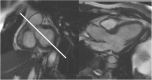

This document is an update to the 2013 publication of the Society for Cardiovascular Magnetic Resonance (SCMR) Board of Trustees Task Force on Standardized Protocols. Concurrent with this publication, 3 additional task forces will publish documents that should be referred to in conjunction with the present document. The first is a document on the Clinical Indications for CMR, an update of the 2004 document. The second task force will be updating the document on Reporting published by that SCMR Task Force in 2010. The 3rd task force will be updating the 2013 document on Post-Processing. All protocols relative to congenital heart disease are covered in a separate document.The section on general principles and techniques has been expanded as more of the techniques common to CMR have been standardized. A section on imaging in patients with devices has been added as this is increasingly seen in day-to-day clinical practice. The authors hope that this document continues to standardize and simplify the patient-based approach to clinical CMR. It will be updated at regular intervals as the field of CMR advances.